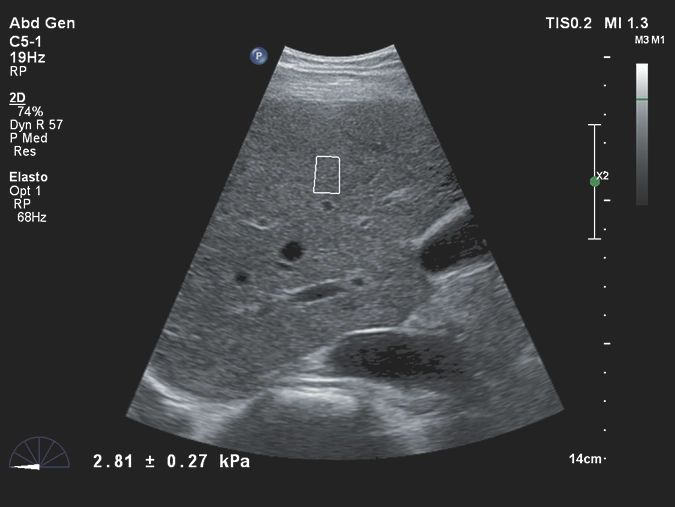

- Абдоминальные исследования

- Эластография сдвиговой волны

- Эластография сдвиговой волной (доп. опция)

Исследования в онкологии

- Strain Elastography - эластография

- Эластография сдвиговой волной для оценки состояния печени

- Компрессионная эластография для молочной железы и органов малого таза